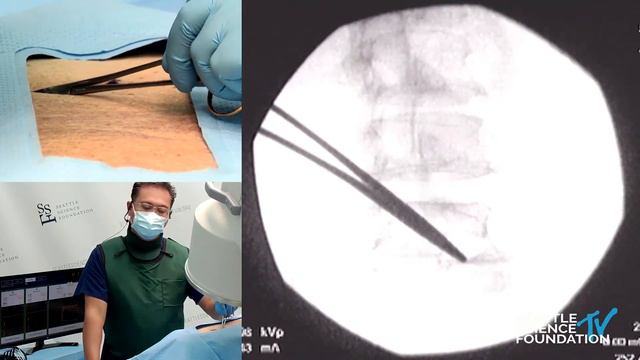

Lumbar and Cervical Medial Branch Neurotomy - Glen David M.D. смотреть онлайн

28:12

Lumbar and Cervical Medial Branch Neurotomy - Glen David M.D.

Бомондистый стадион 14 просмотров